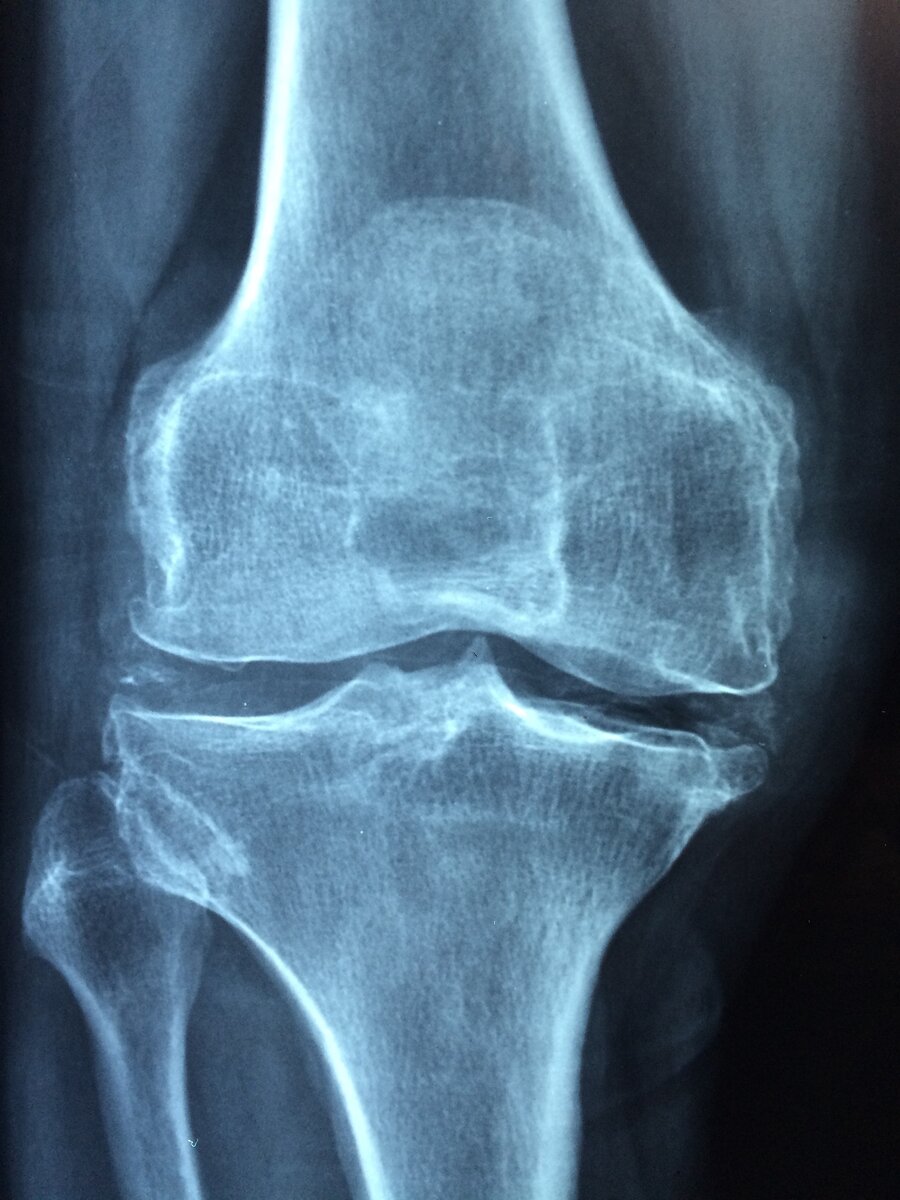

Боли в коленных суставах.

Причины болей в коленях можно условно разделить на 3 типа: